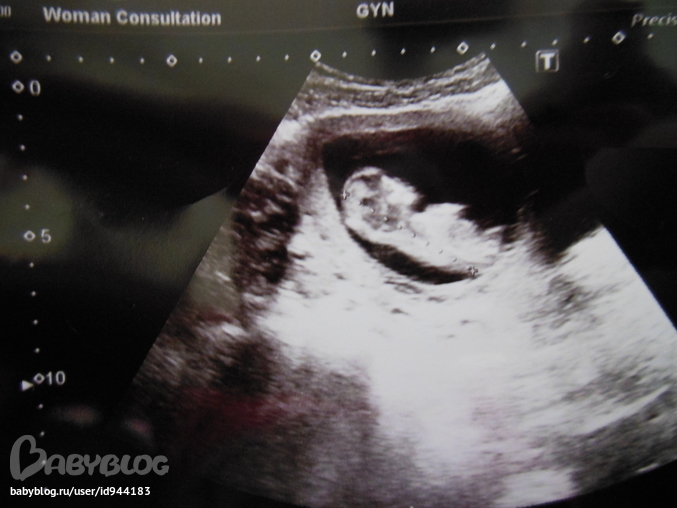

ребеночек 209гр 18 см это было в 18 неделек

Были на узи 21 числа)Знакомила папу с лялей))Не когда не думала что мой любимый муж может расплакаться.Но это случилось когда он увидел нашу кроху

,у него столько эмоций было.

Врача все закидывал вопросами,переживает что ему тесно у меня в животике,все спрашивал что это, а что это такое

Сказали что для своих 18 неделек мы крупные)не по врачебным стандартам )муж говорит мы же особенные,и жена мне богатыря сказала подарит)а врач "А если девочка?" муж "То я и еще одной принцеске буду безумно рад"

когда включили сердечко уже я расплакалась

Ну вот наше солнце

18 см. 209 гр.